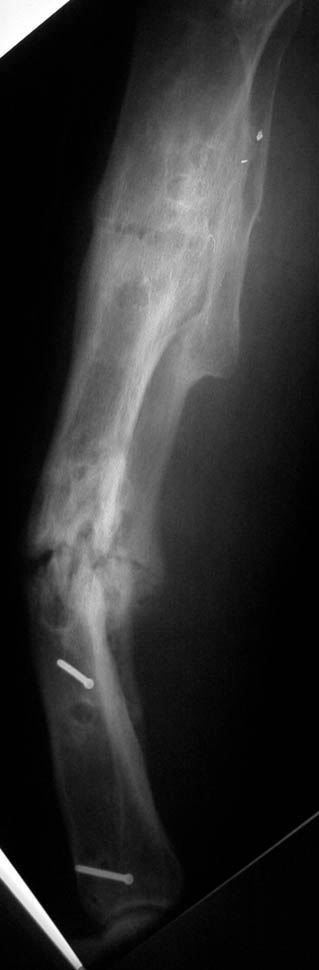

As opposed to the previous Lizard approaches that have been offered, we would take a different tact other than effecting a correction entirely with rings.

With the previously mentioned approaches, we feel that the wires would cut out of the bone as the rings become parallel (it doesn't always work...) - especially if the nonunion is relatively stiff. This would leave a residual, uncorrected deformity with poor bone stock and poor soft tissues. A different Lizard option would be to construct a frame with a ring block at either end, allowing the bone segments to rotate, such that when the apex is PULLED towards it's maximum concavity, the nonunion is compressed as the oblique plane deformity is corrected. It appears as though the lateral cortex is the only worthy structure present in this leg...Utilizing olive wires against this cortex on either side of the nonunion, pulling will maintain constant compression at the nonunion site while minimizing cantilever forces which would result from the use of rings alone were used. If necessary, the lateral cortex could be corticotmized along with the fibula. Click on the figure to enlarge.